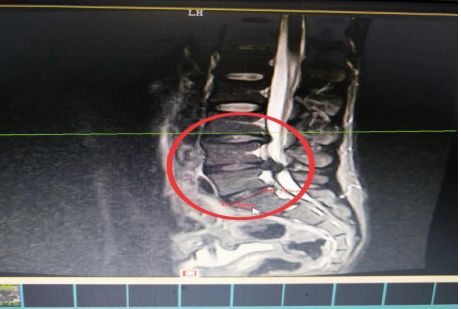

10分鐘后,患者肖先生沒(méi)有家屬陪同的情況下被緊急到骨科一區(qū)病房。接診滿(mǎn)頭大汗、非常緊張肖先生,舒小林醫(yī)師仔細(xì)詢(xún)問(wèn)了病情原來(lái)肖先生從事搬運(yùn)行業(yè),半年前就腰腿痛就醫(yī),當(dāng)時(shí)在保守治療后稍有緩解,沒(méi)有引起重視。直到11月13日下午因搬重物后突然感到腰腿劇烈疼痛、麻木、大小便困難,這才120急救電話(huà)。骨科一區(qū)錢(qián)軍副主任、舒小林醫(yī)師立即給患者作了詳細(xì)的體查,并立即聯(lián)系做急診腰椎磁共振確定有無(wú)神經(jīng)受壓。腰椎磁共振結(jié)果提示:腰4/腰5椎間盤(pán)膨出,導(dǎo)致馬尾神經(jīng)嚴(yán)重受壓,有明顯的手術(shù)指征,如不盡快手術(shù)會(huì)致神經(jīng)受損難以恢復(fù)。錢(qián)軍副主任來(lái)到肖先生病床前,將手術(shù)方案、手術(shù)風(fēng)險(xiǎn)及并發(fā)癥詳細(xì)告知肖先生本人,肖先生表示同意并簽字馬上手術(shù)。

image.png